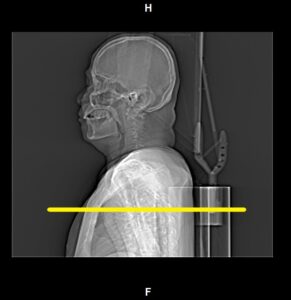

Pre-Monitoring / Contrast Trigger

- Activate the topogram image.

- Place the scan planning line at the level of aortic arch.